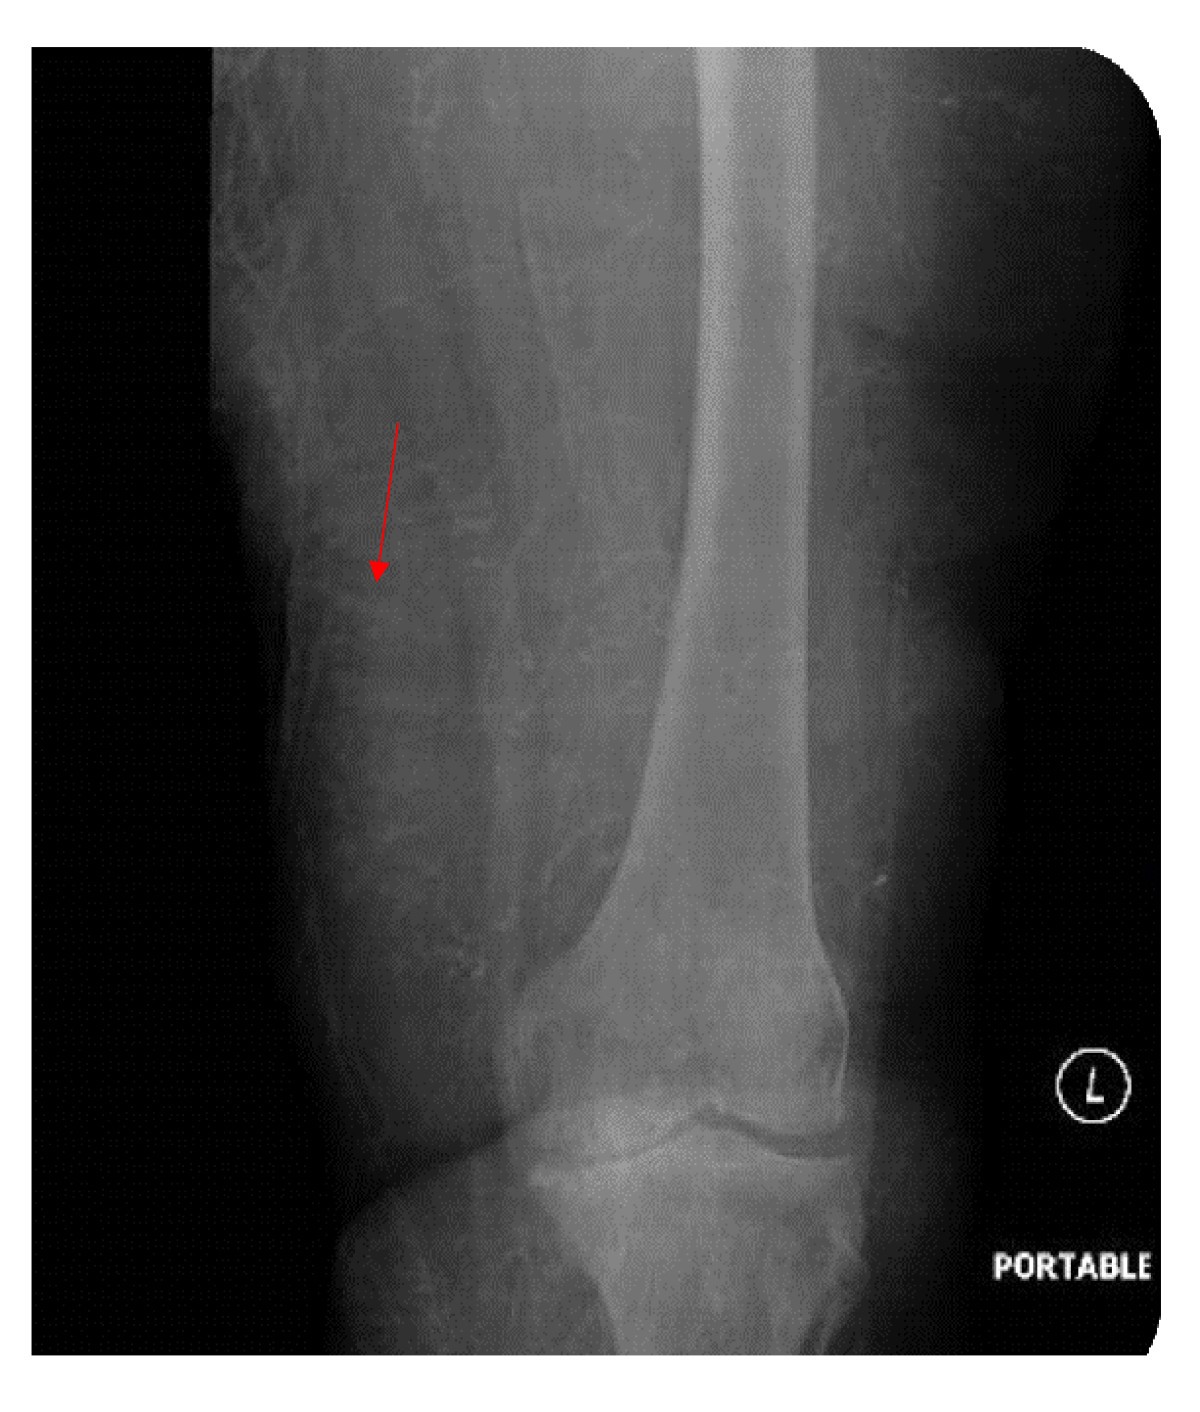

Progressive Ischemic Gangrene in Dialysis Patients: A Clinicopathological Correlation